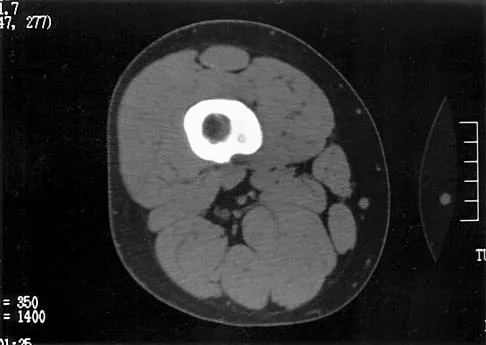

A 46-year-old man has incomplete paraplegia after being involved in a motor vehicle accident. The CT scan shown in Figure 5 reveals marked canal compromise. What is the most appropriate management to improve neurologic status?

Explanation

According to a study by the Scoliosis Research Society, the use of anterior decompression is most predictable for improving neurologic status. This is particularly true of bowel and bladder functional loss. Laminectomy is contraindicated because it further destabilizes the spine. Posterior instrumentation and indirect reduction through distraction and ligamentotaxis only incompletely decompress the compromised canal and are successful only if performed within 48 hours of injury. While some improvement may occur with closed management, the amount of recovery is less than that achieved with surgical decompression. A posterior approach and instrumentation may be added to the anterior decompression based on the characteristics of associated injuries to the posterior element. Gertzbein SD: Scoliosis Research Society multicenter spine fracture study. Spine 1992;17:528-540. Garfin SR, Vaccaro AR (eds): Orthopaedic Knowledge Update: Spine. Rosemont, IL, American Academy of Orthopaedic Surgeons, 1997, pp 197-215.